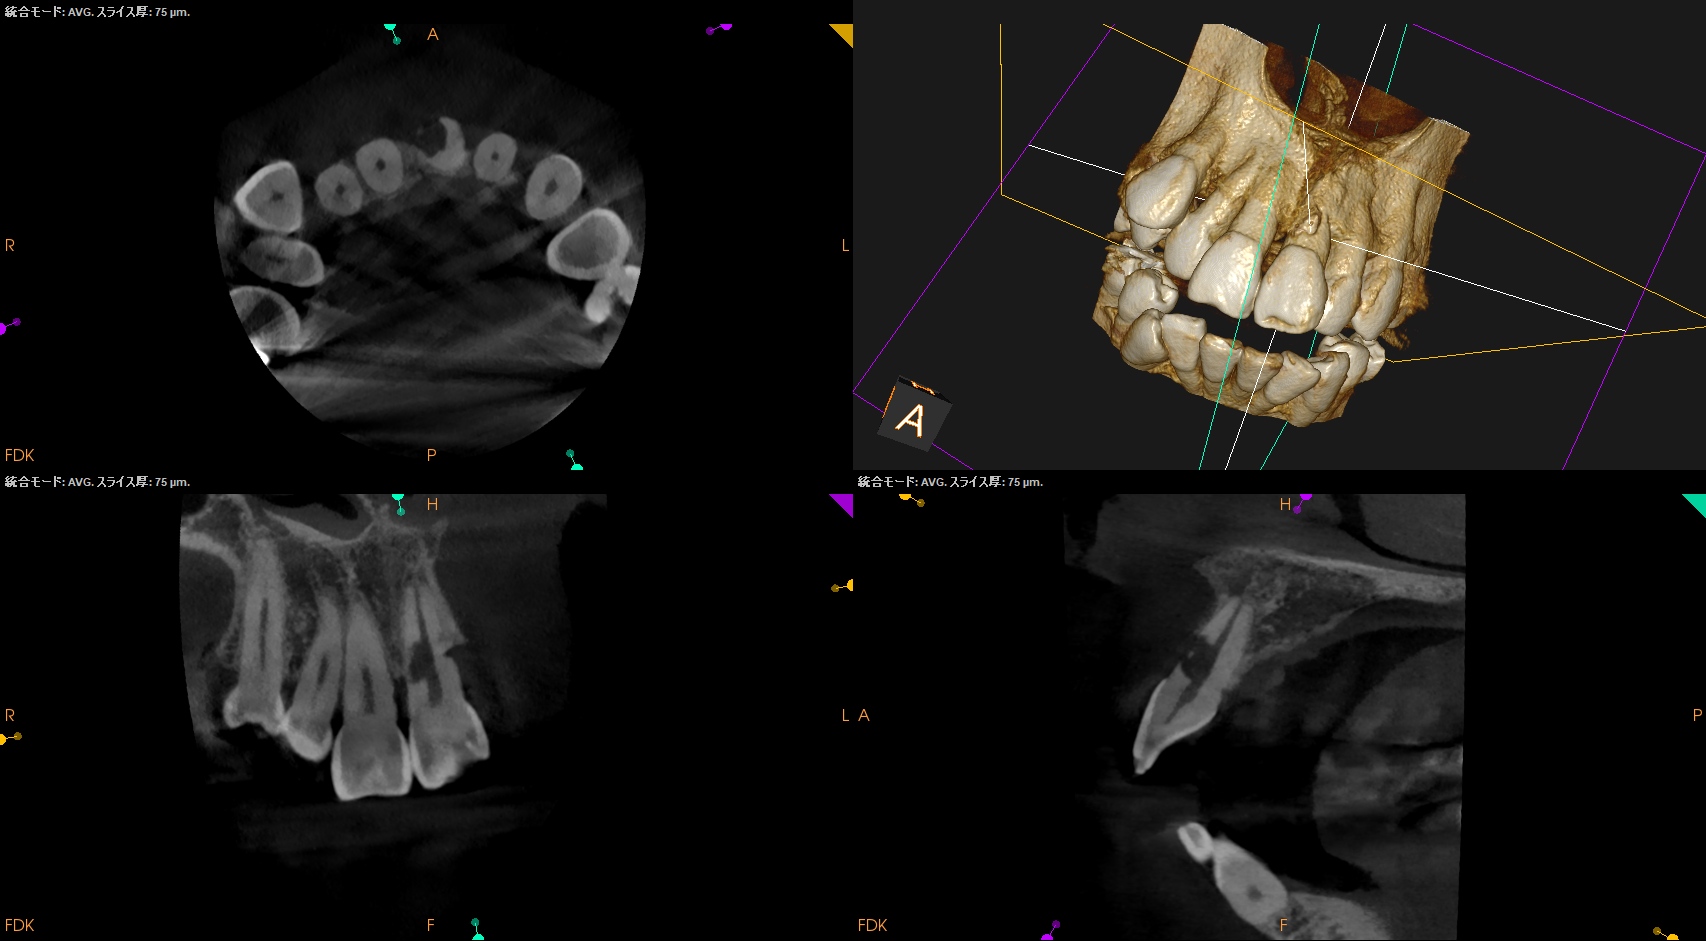

また、CBCTによればそのRIL(Radiographic Instrumentation Length)は23.4mmであるということがわかる。

そこから1mm引いた22.4mm程度が作業長だろう。

このことからもCBCTがなくては治療計画も立てられないということわかるだろう。

まず術前には緑のキシロカインは必須だ。

が、止血しても

外部吸収のRepairを行うときに根管までも封鎖してしまう可能性があるのでそこをどう処理するか?が重要だが、このCBCTの絵からはラバーダム防湿しての根管治療はほぼ無理である。

ということはそういう局面になった場合、唾液が極力入らないような環境で処置しなければらないということわかる。